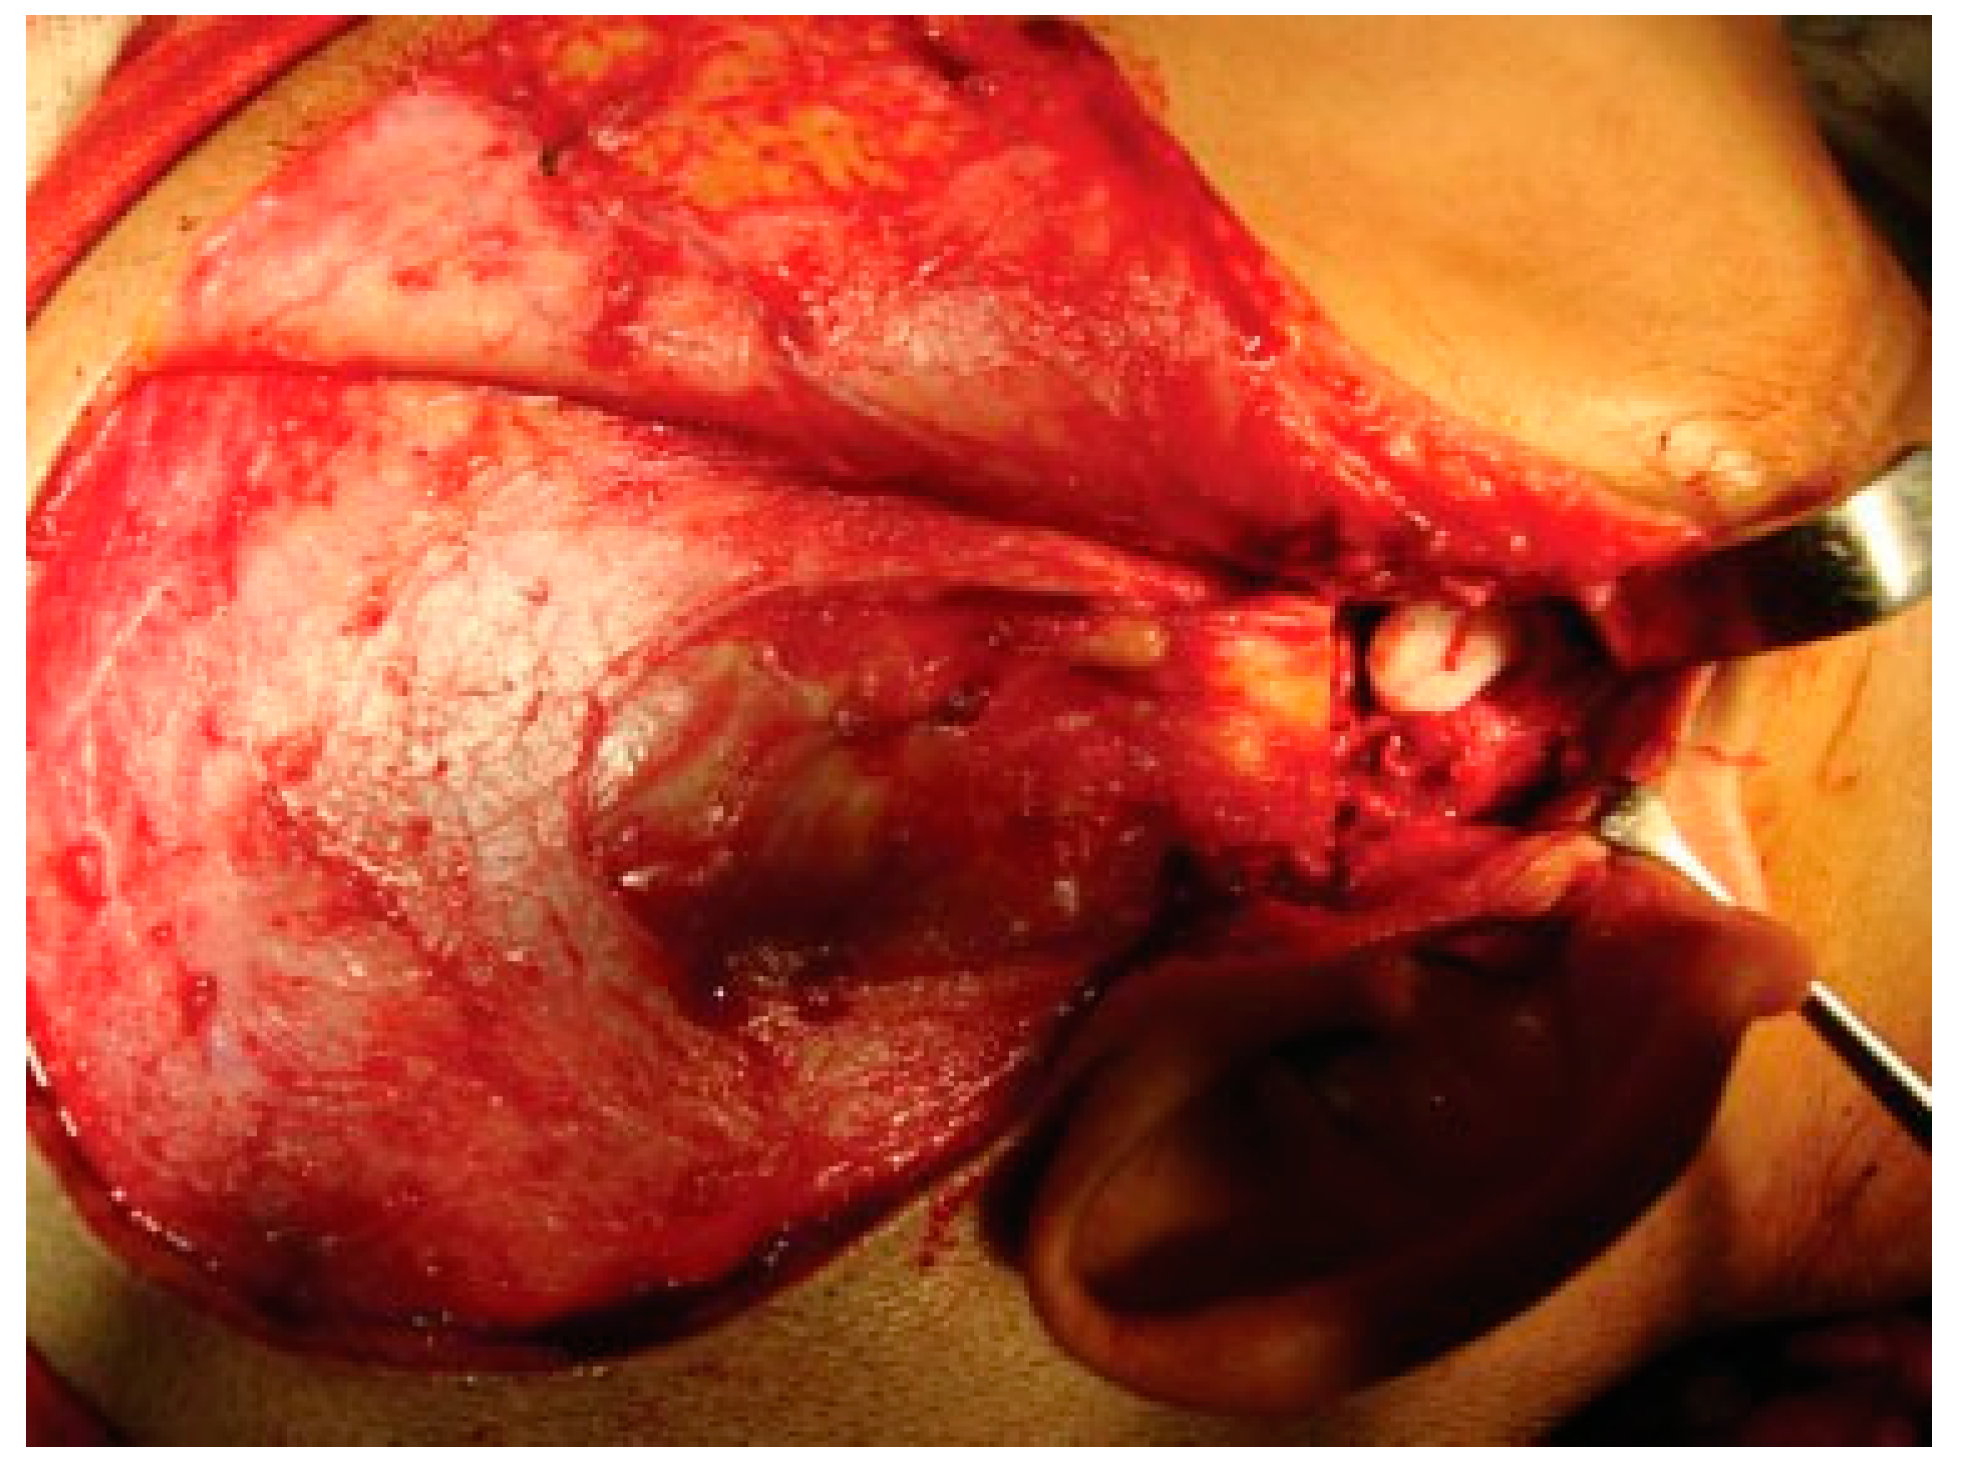

Figure 5. Intraoperative passive mouth opening.

Reconstruction of the TMJ after release of ankylosis assumes paramount importance in terms of restoration of facial form and function. The goals of treatment in all the patients were the release of ankylotic mass, restoration of normal jaw form and function, symmetric growth of the mandible in children, and most importantly the prevention of reankylosis. All interpositional arthroplasties are to some extent the autogenous reconstruction of the morbid ankylotic TMJ after resection of the ankylotic mass. Merriam Webster Dictionary defines reconstruction as the act or process of building something that was damaged or destroyed again. Reconstructive surgery refers to a procedure whose goal is intended to restore form and function in structures deformed or damaged by disease, congenital anomaly, tumor, trauma, or infection (Farlex Partner Medical Dictionary Farlex 2012). The treatment of TMJ ankylosis is individualized based on the severity of ankylosis, age of the patient, and other patient factors. We have outlined our experience following Kaban’s protocol in the management of TMJ ankylosis. It is of paramount importance to obtain passive and maximal mouth opening using this protocol in terms of adequate resection and ipsilateral or contralateral coronoidectomy whenever required followed by aggressive physiotherapy (Figure 5 and Figure 6). Physiotherapy was started on third day postoperatively using Heister mouth gag five times a day during the hospital stay of the patient. This device was purchased by the patient after discharge from the hospital for physiotherapy at home. The MIMO and excursive movements were recorded at various follow-ups for all the patients. No intermaxillary fixation/elastics were applied to any of the patients in the series.